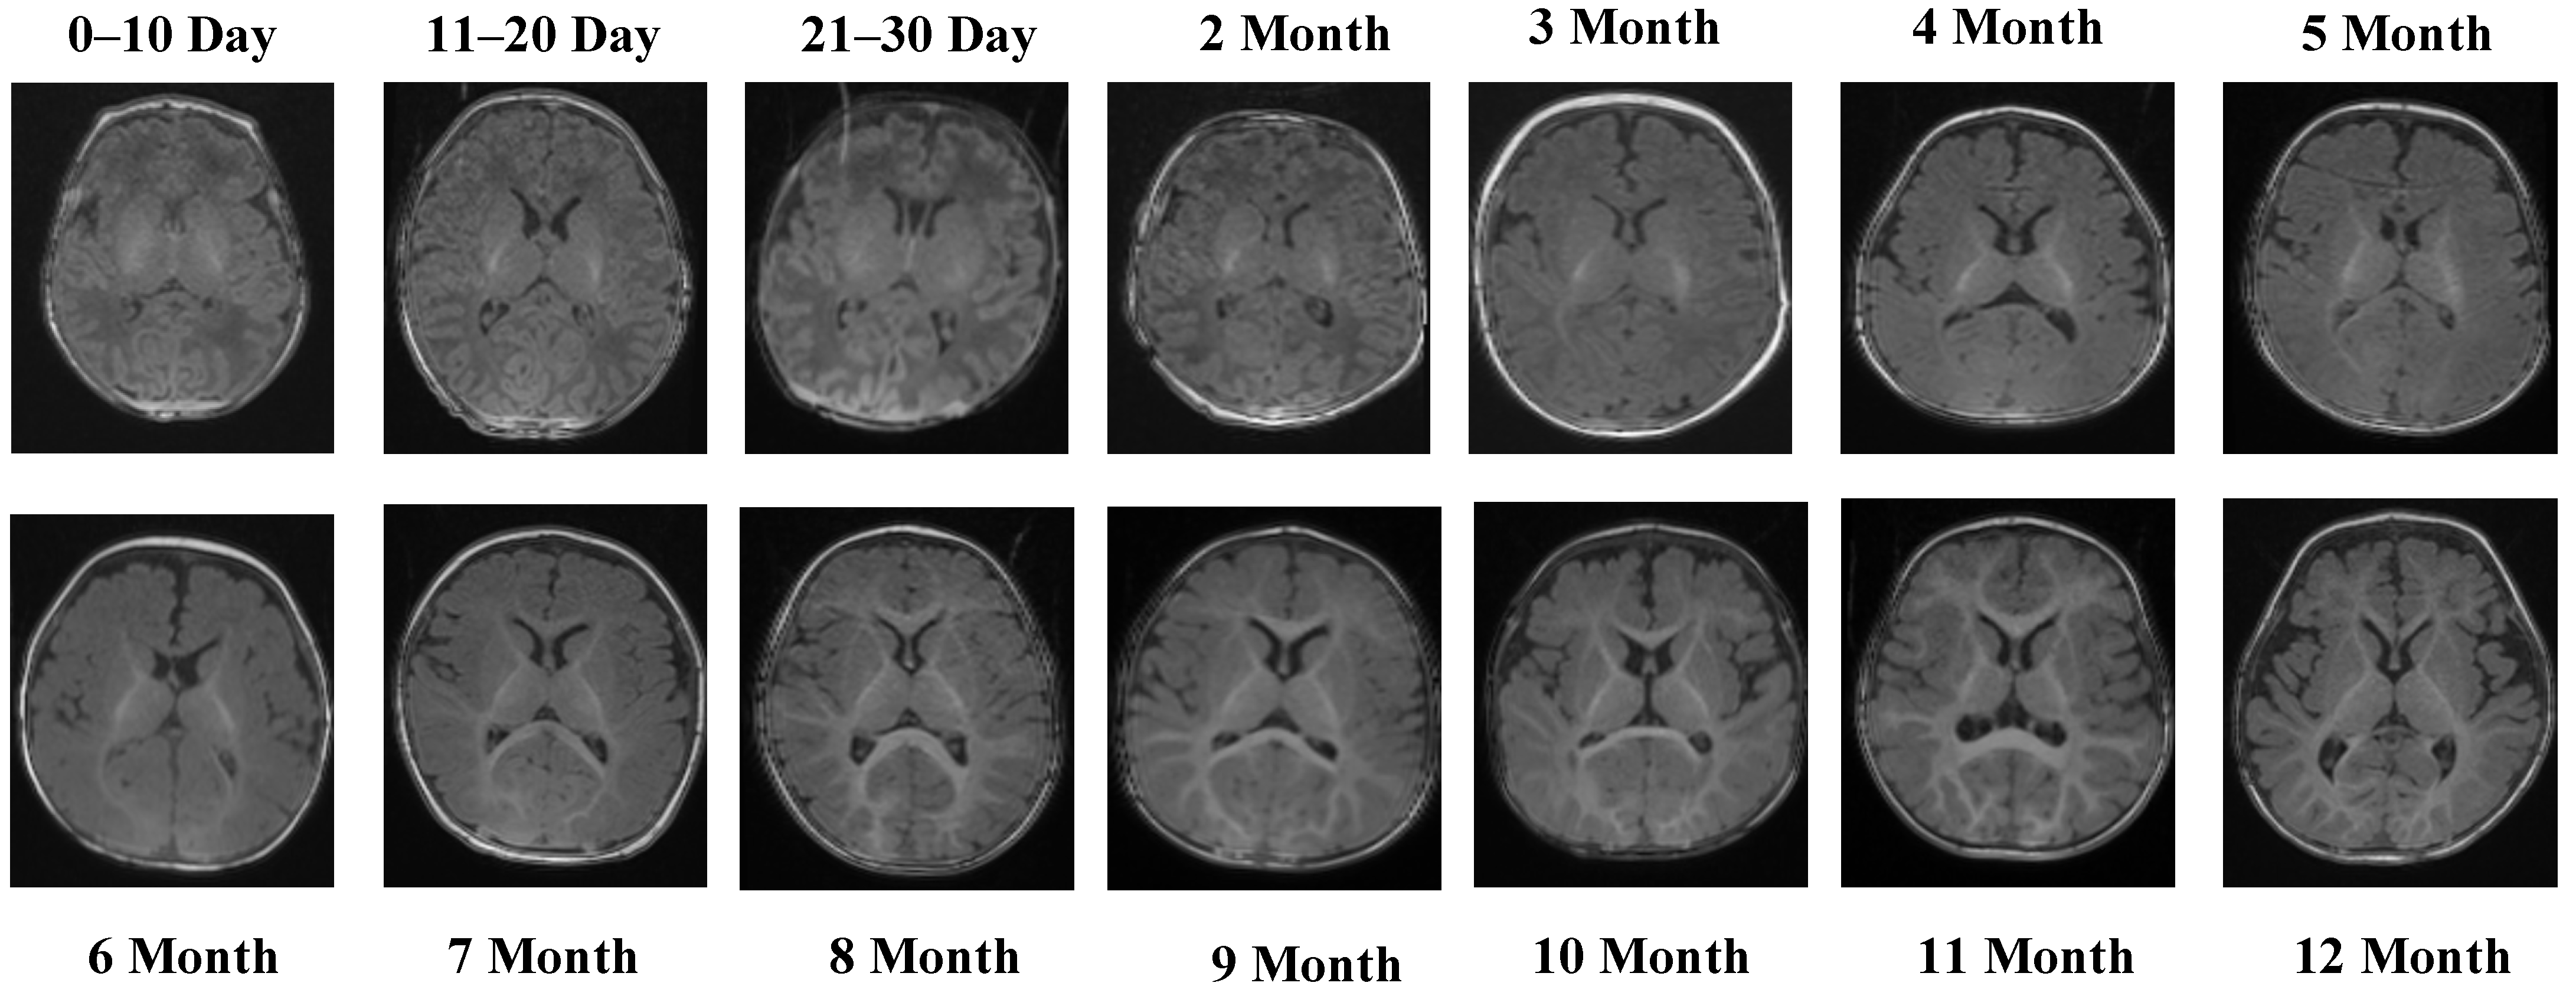

Representative MRI slices from the T1 Male sequence are shown in Figure 1, illustrating anatomical consistency across developmental intervals.

Figure 1 illustrates representative MRI scans from the T1 Male sequence across different developmental groups, highlighting the anatomical consistency and quality of the data.

The T1 Male sequence contained 8154 images (6523 for training and 1631 for testing). The data are systematically organized from early neonatal stages (0–10, 11–20, and 21–30 days) to monthly intervals covering 2–12 months. This structured arrangement provides balanced coverage across both early infancy and later developmental stages. Examples of MRI slices from the T1 Female sequence are presented in Figure 2, demonstrating structural variation across neonatal and infant periods.